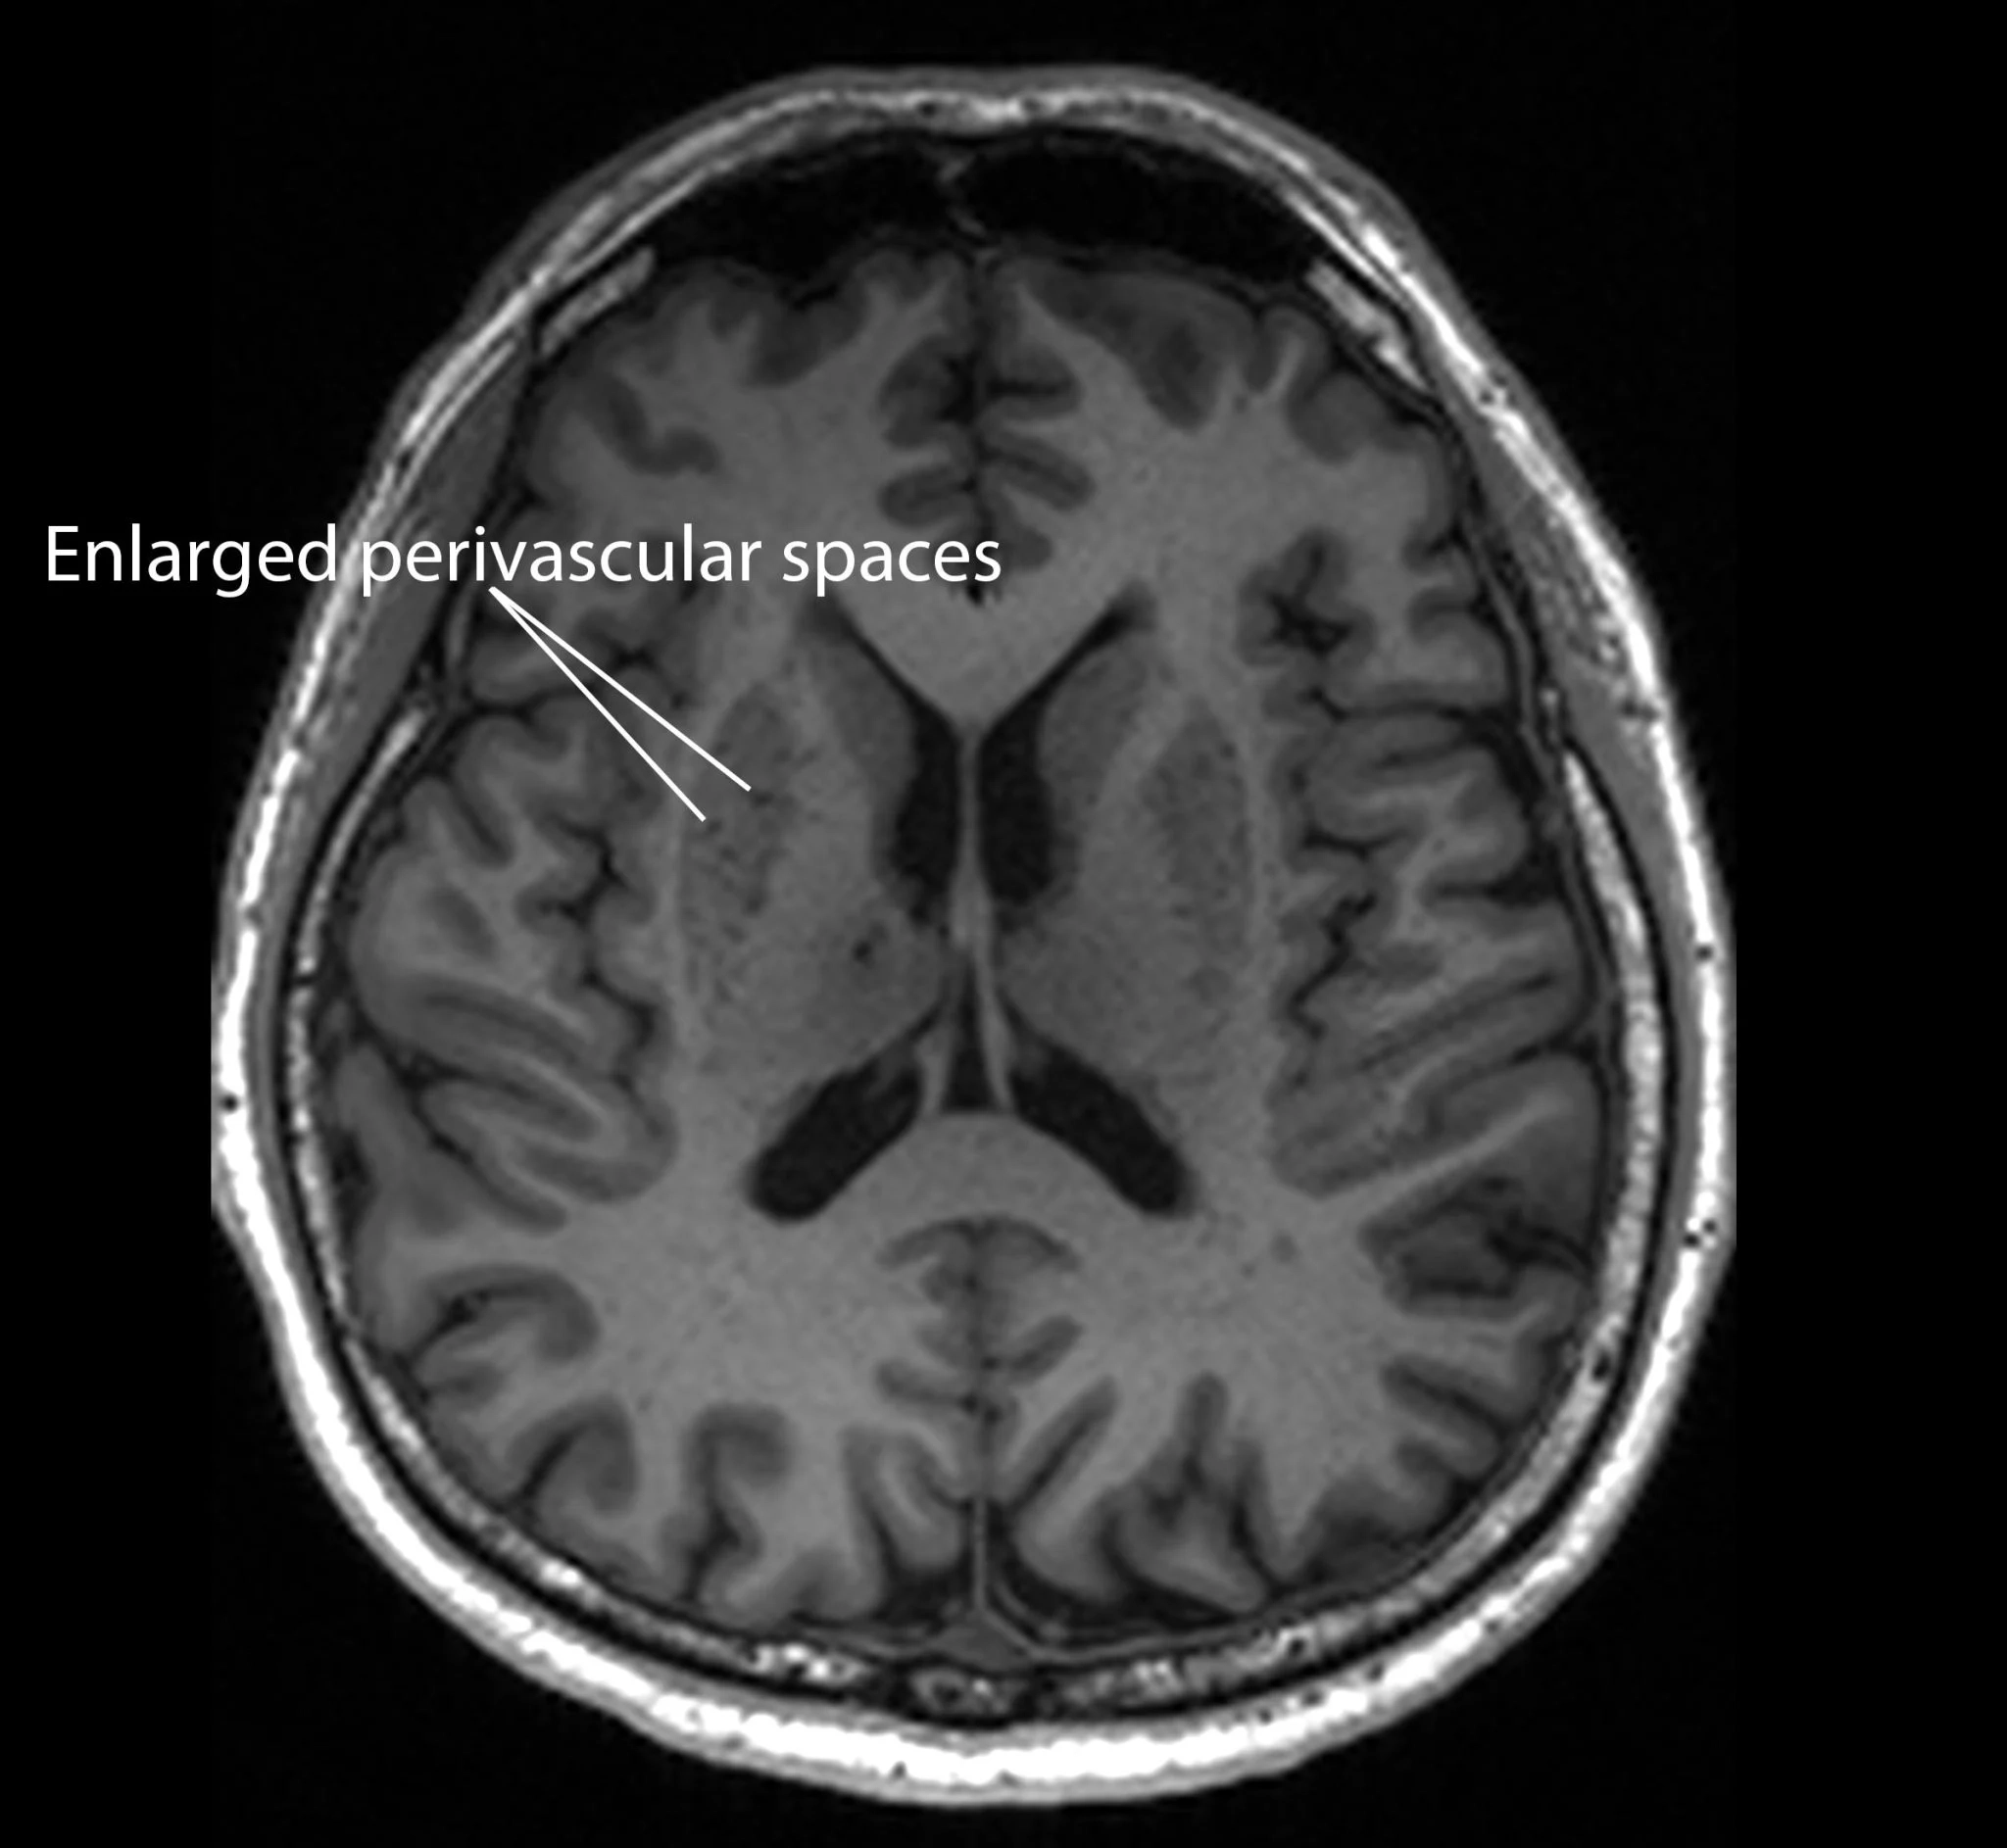

Dünya genelinde yaşlanan nüfusla birlikte artan bunama ve Alzheimer vakalarına karşı bilim dünyası, erken teşhis yöntemlerine odaklanmış durumda. NTU Lee Kong Chian Tıp Fakültesi (LKCMedicine) tarafından yürütülen ve Asya popülasyonuna odaklanan kapsamlı bir çalışma, beyindeki ‘genişlemiş perivasküler boşluklar’ ile bilişsel gerileme arasında doğrudan bir bağlantı olduğunu ortaya koydu.

Beynin kan damarlarını çevreleyen bu mikro kanallar, Alzheimer hastalarında biriken beta amiloid ve tau proteinleri gibi zararlı atıkların temizlenmesinde kritik rol oynuyor. Sistem verimsizleşip tıkandığında ise bu boşluklar genişleyerek MR görüntülerinde belirgin hale geliyor.

Araştırmacılar, katılımcıların MR taramalarını ve kan değerlerini analiz etti. Hafif bilişsel bozukluğu olan bireylerde, beyin drenaj kanallarındaki tıkanıklıkların (genişlemiş perivasküler boşluklar), Alzheimer ile ilişkili biyokimyasallarla olan bağlantısının, geleneksel olarak bakılan ‘beyaz cevher hasarına’ kıyasla daha güçlü olduğu görüldü.

Bu bulgu, genişlemiş perivasküler boşlukların, hastalığın biyokimyasal belirtileriyle (amiloid plak ve tau yumakları) doğrudan ilişkili olduğunu ve kalıcı beyin hasarı oluşmadan önce bir erken uyarı sistemi olarak kullanılabileceğini gösteriyor.